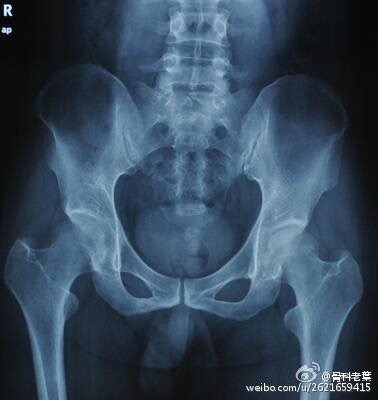

0期 病人有髋部症状,但是X线片与磁共振正常

I期 病人有髋部症状,X线片正常,磁共振出现异常